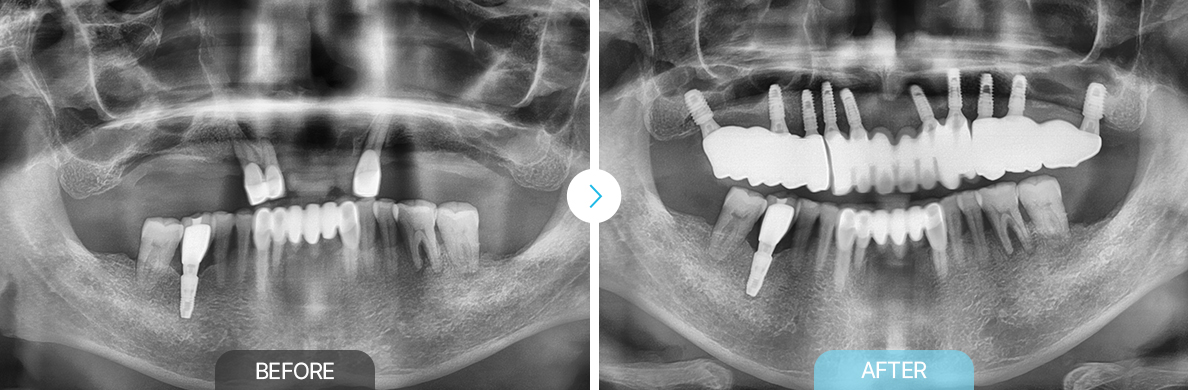

임플란트/틀니

BEFOREAFTERBEFOREAFTERBEFOREAFTERBEFOREAFTER